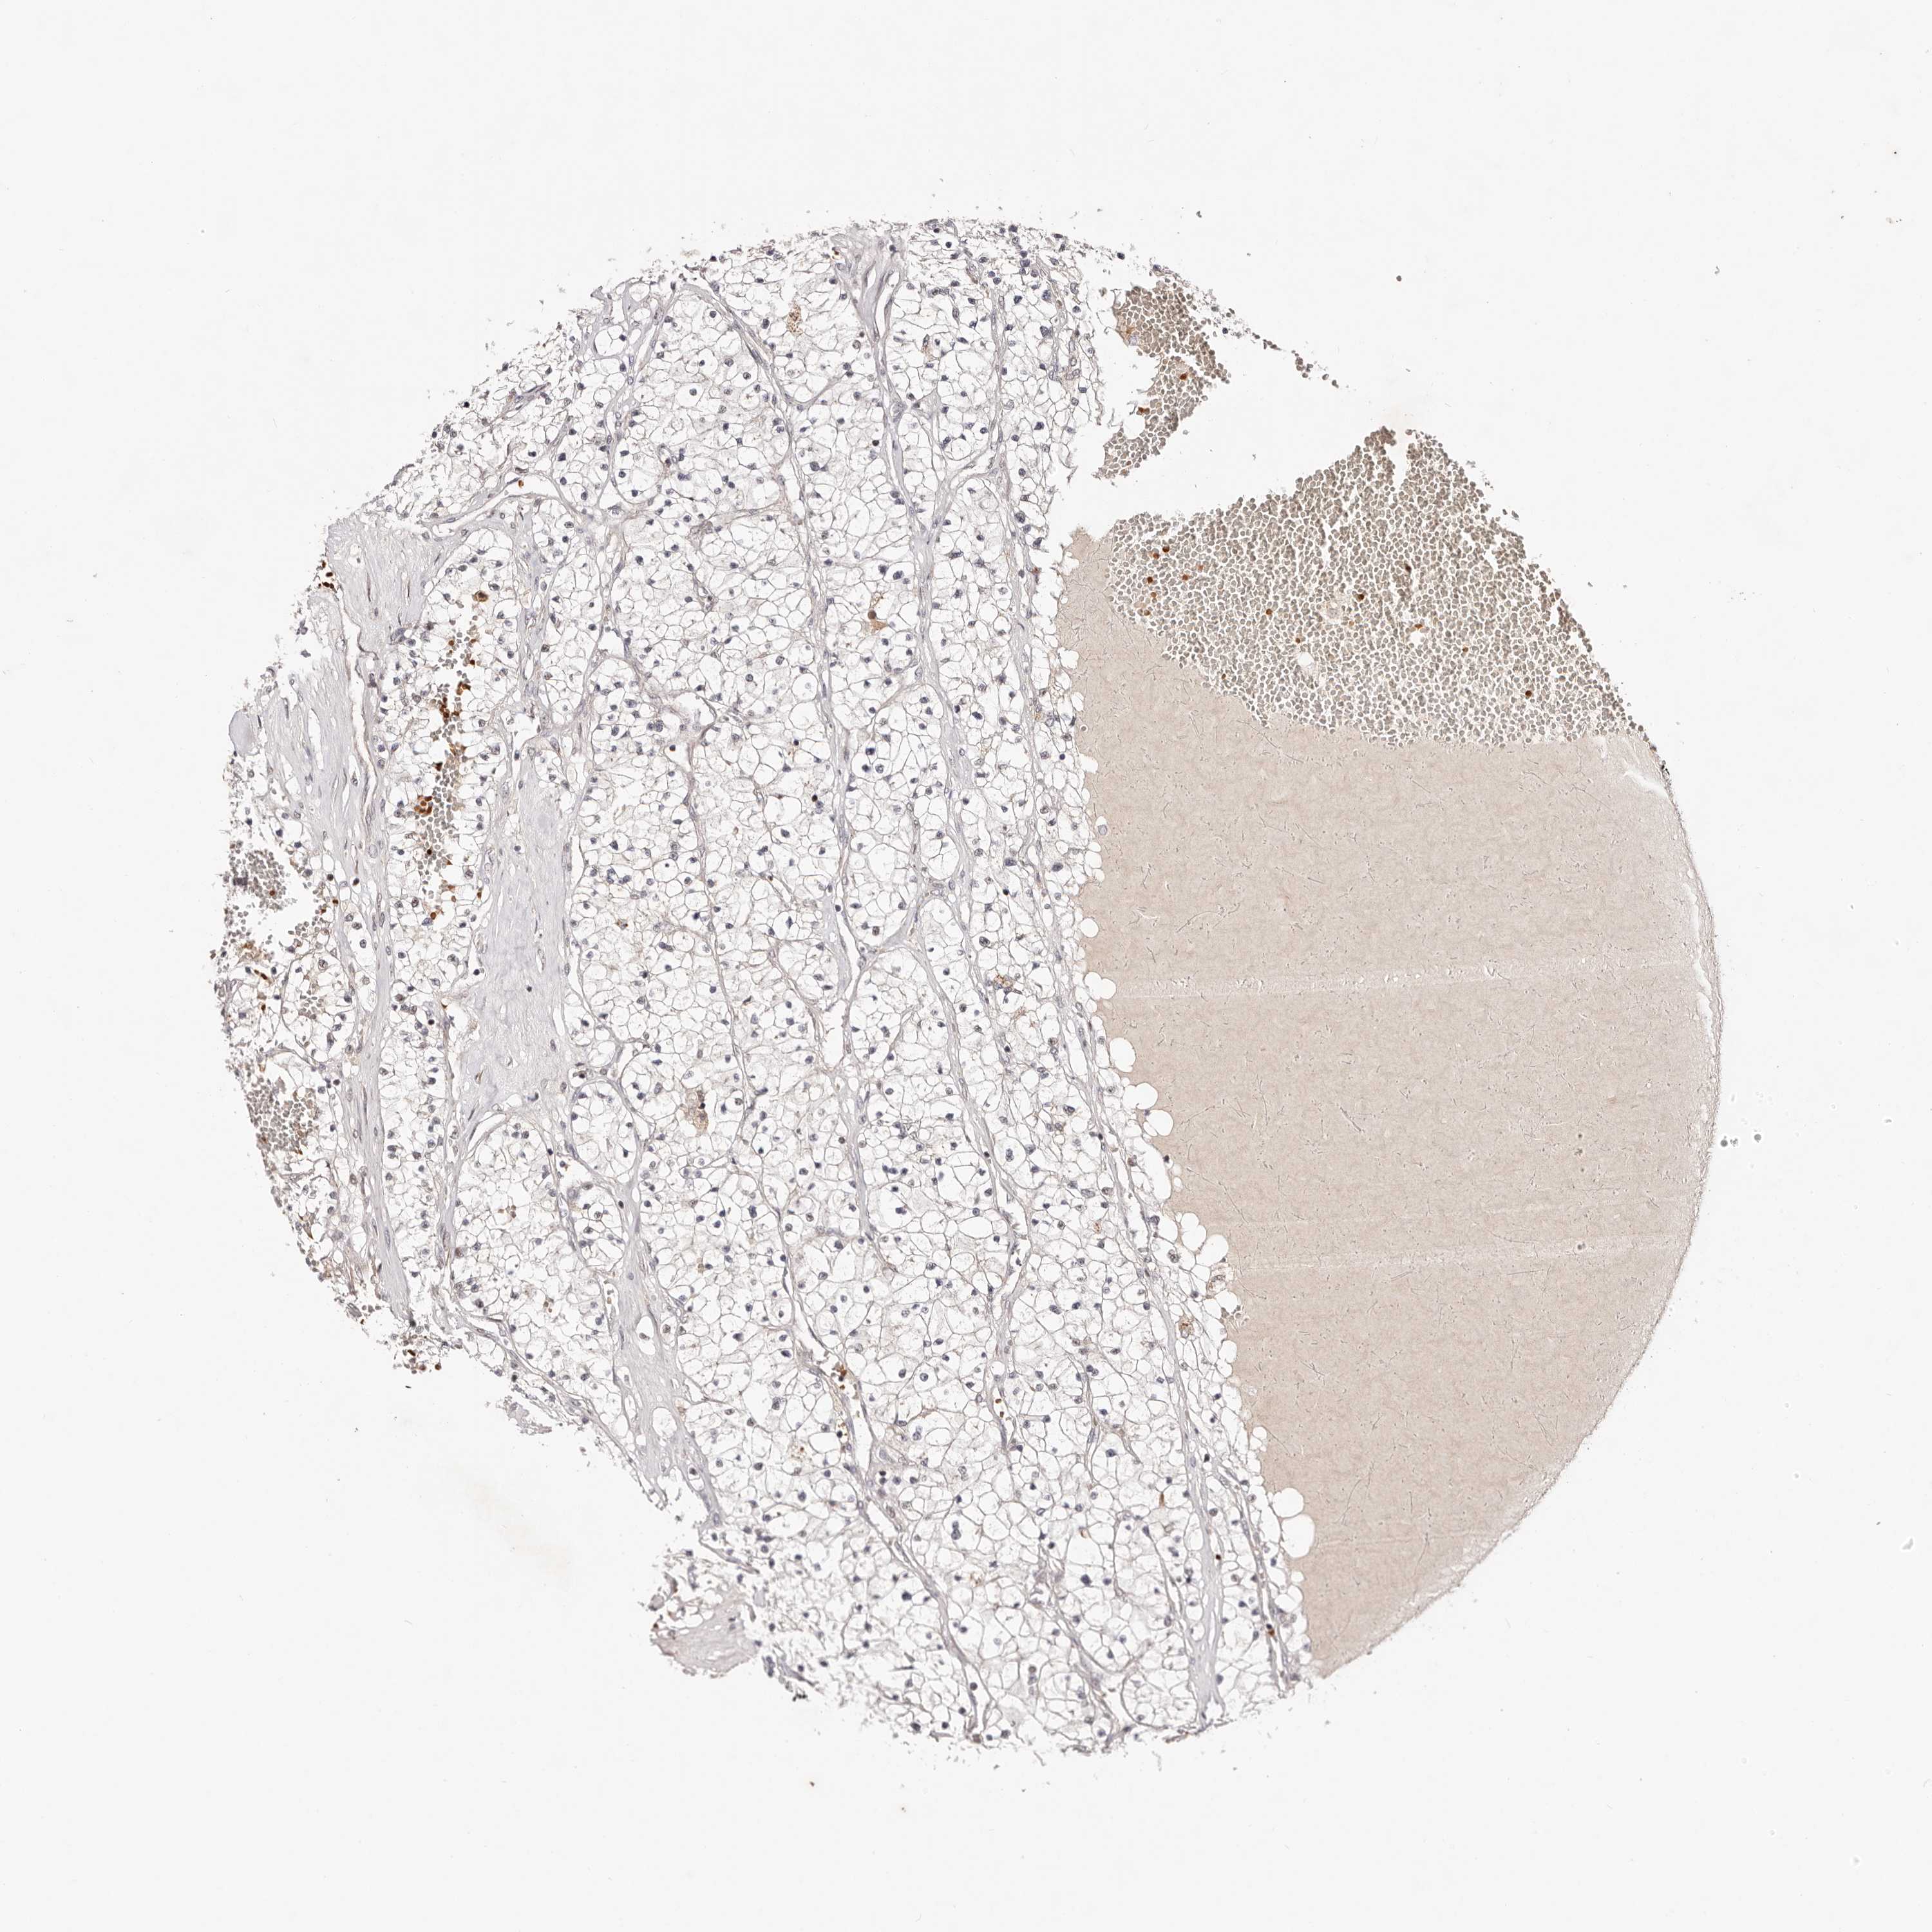

KIDNEY RENAL CLEAR CELL CARCINOMA (VALIDATION) - Interactive survival scatter ploti

The Survival Scatter plot shows the clinical status (i.e. dead or alive) for all individuals in the patient cohort, based on the same data that underlies the corresponding Kaplan-Meier plots. Patients that are alive at last time for follow-up are shown in blue and patients who have died during the study are shown in red.

The x-axis shows the expression levels (FPKM) of the investigated gene in the tumor tissue at the time of diagnosis. The y-axis shows the follow-up time after diagnosis (years). Both axes are complimented with kernel density curves demonstrating the data density over the axes. The top density plot shows the expression levels (FPKM) distribution among dead (red) and alive patients (blue). The right density plot shows the data density of the survived years of dead patients with high and low expression levels respectively, stratified using the cutoff indicated by the vertical dashed line through the Survival Scatter plot. This cutoff is automatically defined based on the FPKM cutoff that minimizes the p-score. The cutoff can be changed by dragging the vertical line or by entering a cutoff value in the square labeled "Current cut-off".

Under the Survival Scatter plot the p-score landscape (black curve; left axis) is shown together with dead median separation (red curve; right axis). Dead median separation is the difference in median mRNA expression between patients who have died with high and low expression, respectively. It is calculated as follows: median FPKM expression of dead patients with high expression - median FPKM expression of dead patients with low expression. This is intended to aid the user in visually exploring custom cutoffs and the associated p-scores and dead median separation.

Individual patient data is displayed and can be filtered by clicking on one or more of the category buttons on the top of the page. Categories describing expression level and patient information include: high, low, alive, dead, female, male and tumor stages. The scale of the x-axis can be toggled between linear and log-scale by clicking on the "x log" button. Mouse-over function shows TCGA ID, patient information and mRNA expression (FPKM) for each patient.

& Survival analysisi

Kaplan-Meier plots summarize results from analysis of correlation between mRNA expression level and patient survival. Patients were divided based on level of expression into one of the two groups "low" (under cut off) or "high" (over cut off). X-axis shows time for survival (years) and y-axis shows the probability of survival, where 1.0 corresponds to 100 percent.

WRN is not prognostic in Kidney Renal Clear Cell Carcinoma (validation)

Best expression cut offi

Based on the FPKM value of each gene, patients were classified into two groups and association between prognosis (survival) and gene expression (FPKM) was examined. The best expression cut-off refers the FPKM value that yields maximal difference with regard to survival between the two groups at the lowest log-rank P-value. Best expression cut-off was selected based on survival analysis .

When clicking on this number, the vertical dashed line indicating cut-off, the interactive survival plot, and the Kaplan-Meier curve will be adjusted to show results based on the best expression cut-off.

: 2.41

P scorei

Log-rank P value for Kaplan-Meier plot showing results from analysis of correlation between mRNA expression level and patient survival.

N/A

Average pTPM 3.0

Number of samples 100